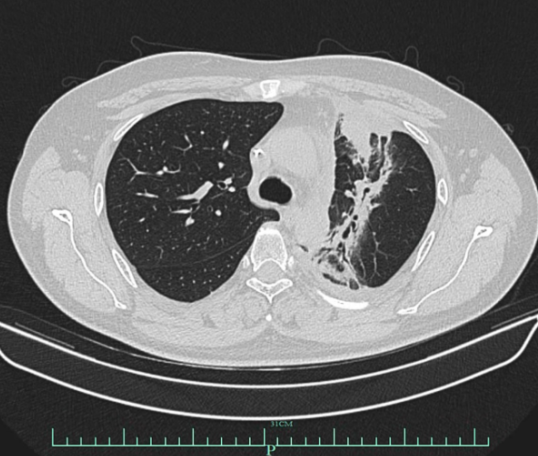

3、2023-02-27、2023-3-20行斯鲁利单抗免疫单药维持治疗2周期。2023-04完善胸部CT,提示左肺上叶炎症,结合病史,考虑放射性肺炎,暂停免疫治疗1次。

影像学检查图像